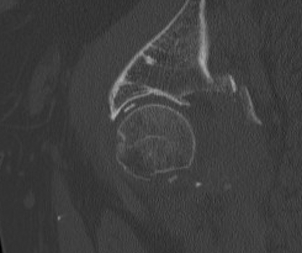

Pathoanatomy

Capsule & Ligamentum teres torn

Labral tears & muscular injuries also occur

Y / iliofemoral ligament often intact with posterior dislocation

- blocks reduction

- bony fragments also block reduction

3. Screen for retained fragments

Compulsory CT

- xray will not detect fragments < 2mm

Non-concentric Reduction

CT

- only with CT can < 2mm fragments be seen

MRI

- may be needed to see labral tears blocking reduction